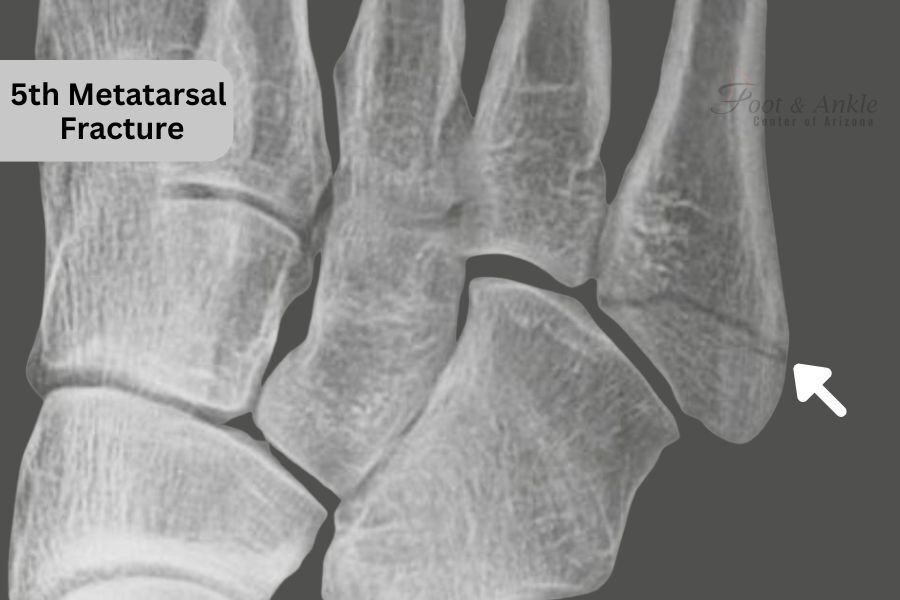

How is a hairline fracture of the fifth metatarsal identified?

A healthcare professional, including Dr. Kris A. DiNucci, DPM, FACFAS, will perform a bodily examination and might order imaging exams like X-rays or MRI to confirm the analysis.